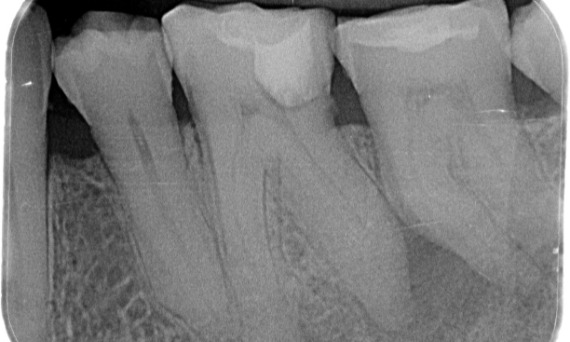

Before: Periapical radiolucency associated primarily with the distal root and loss of lamina dura on the mesial root.

After: TruNatomy was chosen in this case to allow a caries leveraged approach and a focus on pericervical dentin preservation especially on the mesial aspect where the tooth had a more minimal restoration.

Bath, UK

"A patient and process centered success." - Dr. Cowie